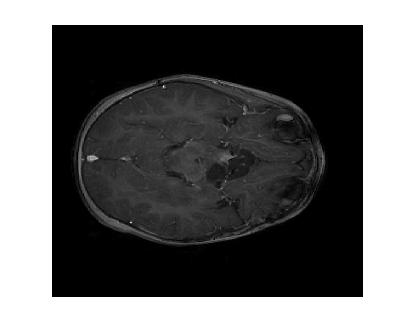

Due to its wide use in image processing, we consider the use of gradient sparsification with LACS-MRI. We show below that it is possible to produce image reconstructions with significantly higher Reconstruction SNR using gradient sparsification. We have repeated some of the simulations from above for different compression levels, , using the gradient transform to sparsify instead of the wavelet transform. We will refer to this as ”LACS-MRI with gradient sparsity.” We compared the performance of each sparsification method at each compression level using LACS-MRI and then compared this to the L1-W method. Again, we use a reference image and a follow-up image that we hope to recover as in Figure 8. We consider here only the phantom image, as it serves as a prime candidate for gradient sparsification, and is small enough that evaluation of all PDFs is computationally feasible.

We re-ran simulations for cases 7, 8, 17, and 18 on the phantom. Over 30 trials, using the gradient on the phantom image resulted in much higher RSNR for every single case. Cases 7 and 17 both also outperformed cases 8 and 18 every time by about 13%. These cases both used the variable density sampling method and LACS-MRI. Figure 9 shows the reconstruction from Case 17. The recovered image using LACS-MRI with wavelet sparsity is more pixelated near the tumor while LACS-MRI with gradient sparsity produced an almost perfect reconstruction. Figure 11 shows the great disparity between the two sparsifying methods. On average, the four phantom reconstructions using the gradient only needed to sample about 6% of the data to achieve the same RSNR that the reconstructions using the wavelets did at 21% sampling.

We also compare the LACS-MRI gradient method to the Cases 9 and 10 which use -minimization with wavelet sparsity. Clearly, the L1-W method recovered the phantom image very poorly, as shown in Figure 10 and Figure 11 (b). The image is blurry even when 18% of the available data was sampled. The RSNR of L1-W is worse than both the RSNR achieved by LACS-MRI with wavelet sparsity and LACS-MRI with gradient sparsity.

We can conclude from these experiments that different sparsification methods can clearly have a drastic effect on the reconstruction of the follow-up image. LACS-MRI with gradient sparsity is better for images with a sparser gradient than wavelet transform, such as the phantom image. For images with high amounts of texture we expect the wavelet transform to work better. Therefore, if we know that an image will be more sparse in one domain over the other, we can appropriately choose the reconstruction method. Such a determination of course may be non-trivial in some applications, and much research in compressed sensing and sparse approximation focuses on this judgement.